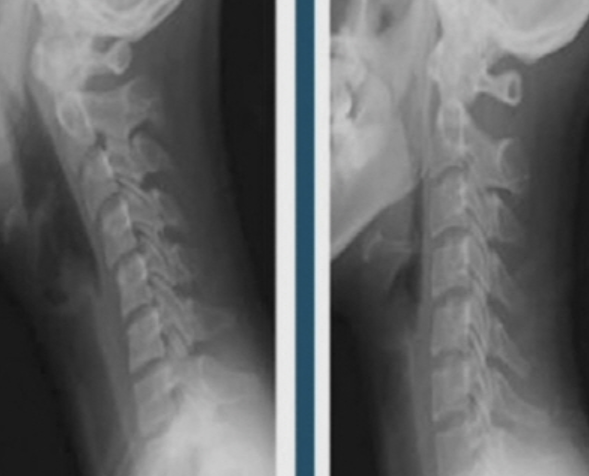

진단

▶ X-ray와 근전도 검사로 초기 확인이 가능합니다.

▶ 정확한 진단을 위해서는 MRI 검사가 필요합니다.